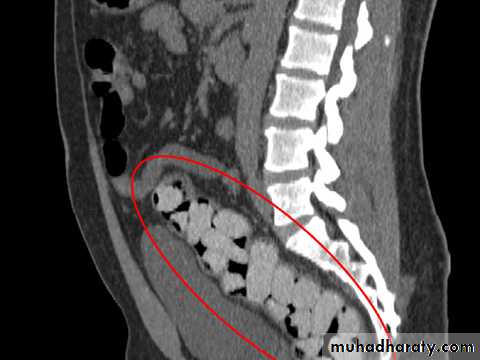

C-Radiographic examination:

-Limited role.-Lack of Radiopacity. (Undetectable by x ray).

-Plain X ray Of the Abdomen.

-CT Scan.

Foreign Body in GIT (Body packers)Latex plastic storage.